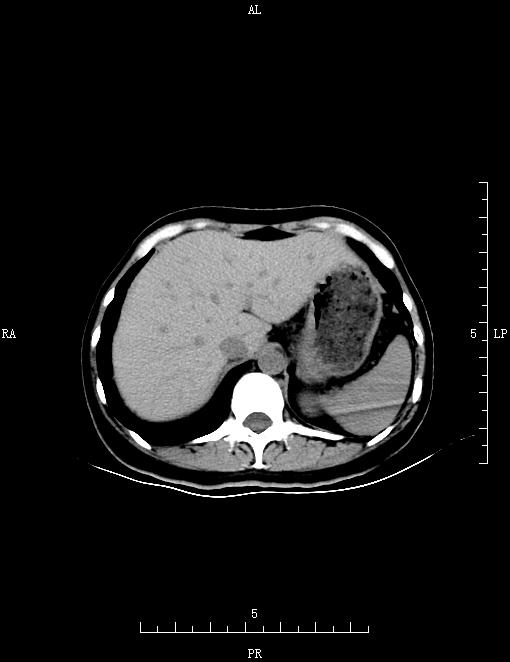

CT53102:双肾输尿管膀胱CT

女,41岁,间断性血尿20天,为初始血尿,运动后加重。

肝内胆管扩张,子宫颈增大且外形欠规整,左侧附件区似见低密度影,子宫周围及直肠窝见液体密度影。考虑:子宫颈占位可疑,建议MRI检查。左侧附件区囊肿?盆腔积液。

是血尿?阴道流血?本CT片泌尿系未见异常。另:子宫轮廓 内膜 颈部似不甚规则。另:子宫周围明显见积液。子宫左侧旁似见囊肿。余无特记。建议增强,待除外子宫病变。另:1、左侧卵巢囊肿不排除。2、盆腔炎。

宫颈癌不排除,建议核磁